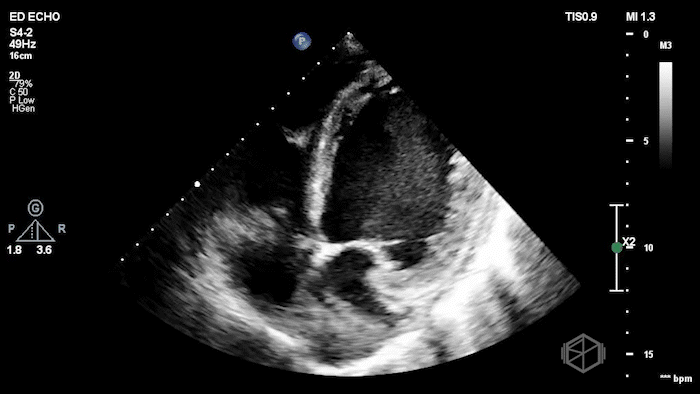

Dr. Herzog was working at NYU Suffolk where he had a mid 60โ€™s female with reportedly only a past medical history of anxiety (recently diagnosed) presenting to the ED with anxious sensation, triaged for anxiety. The patient was slightly tachycardic and mild respiratory distress. Dr. Herzog grabbed the US and saw the following:

The POCUS shows an extremely low EF, about 15-20% visually, with a plethoric IVC. The patient had a cath that showed mild non-obstructive coronary disease and she was determined to have non-ischemic cardiomyopathy due to unknown etiology, possibly viral infection vs. stress related.

Diagnosis: New onset congestive heart failure with significantly reduced ejection fraction.